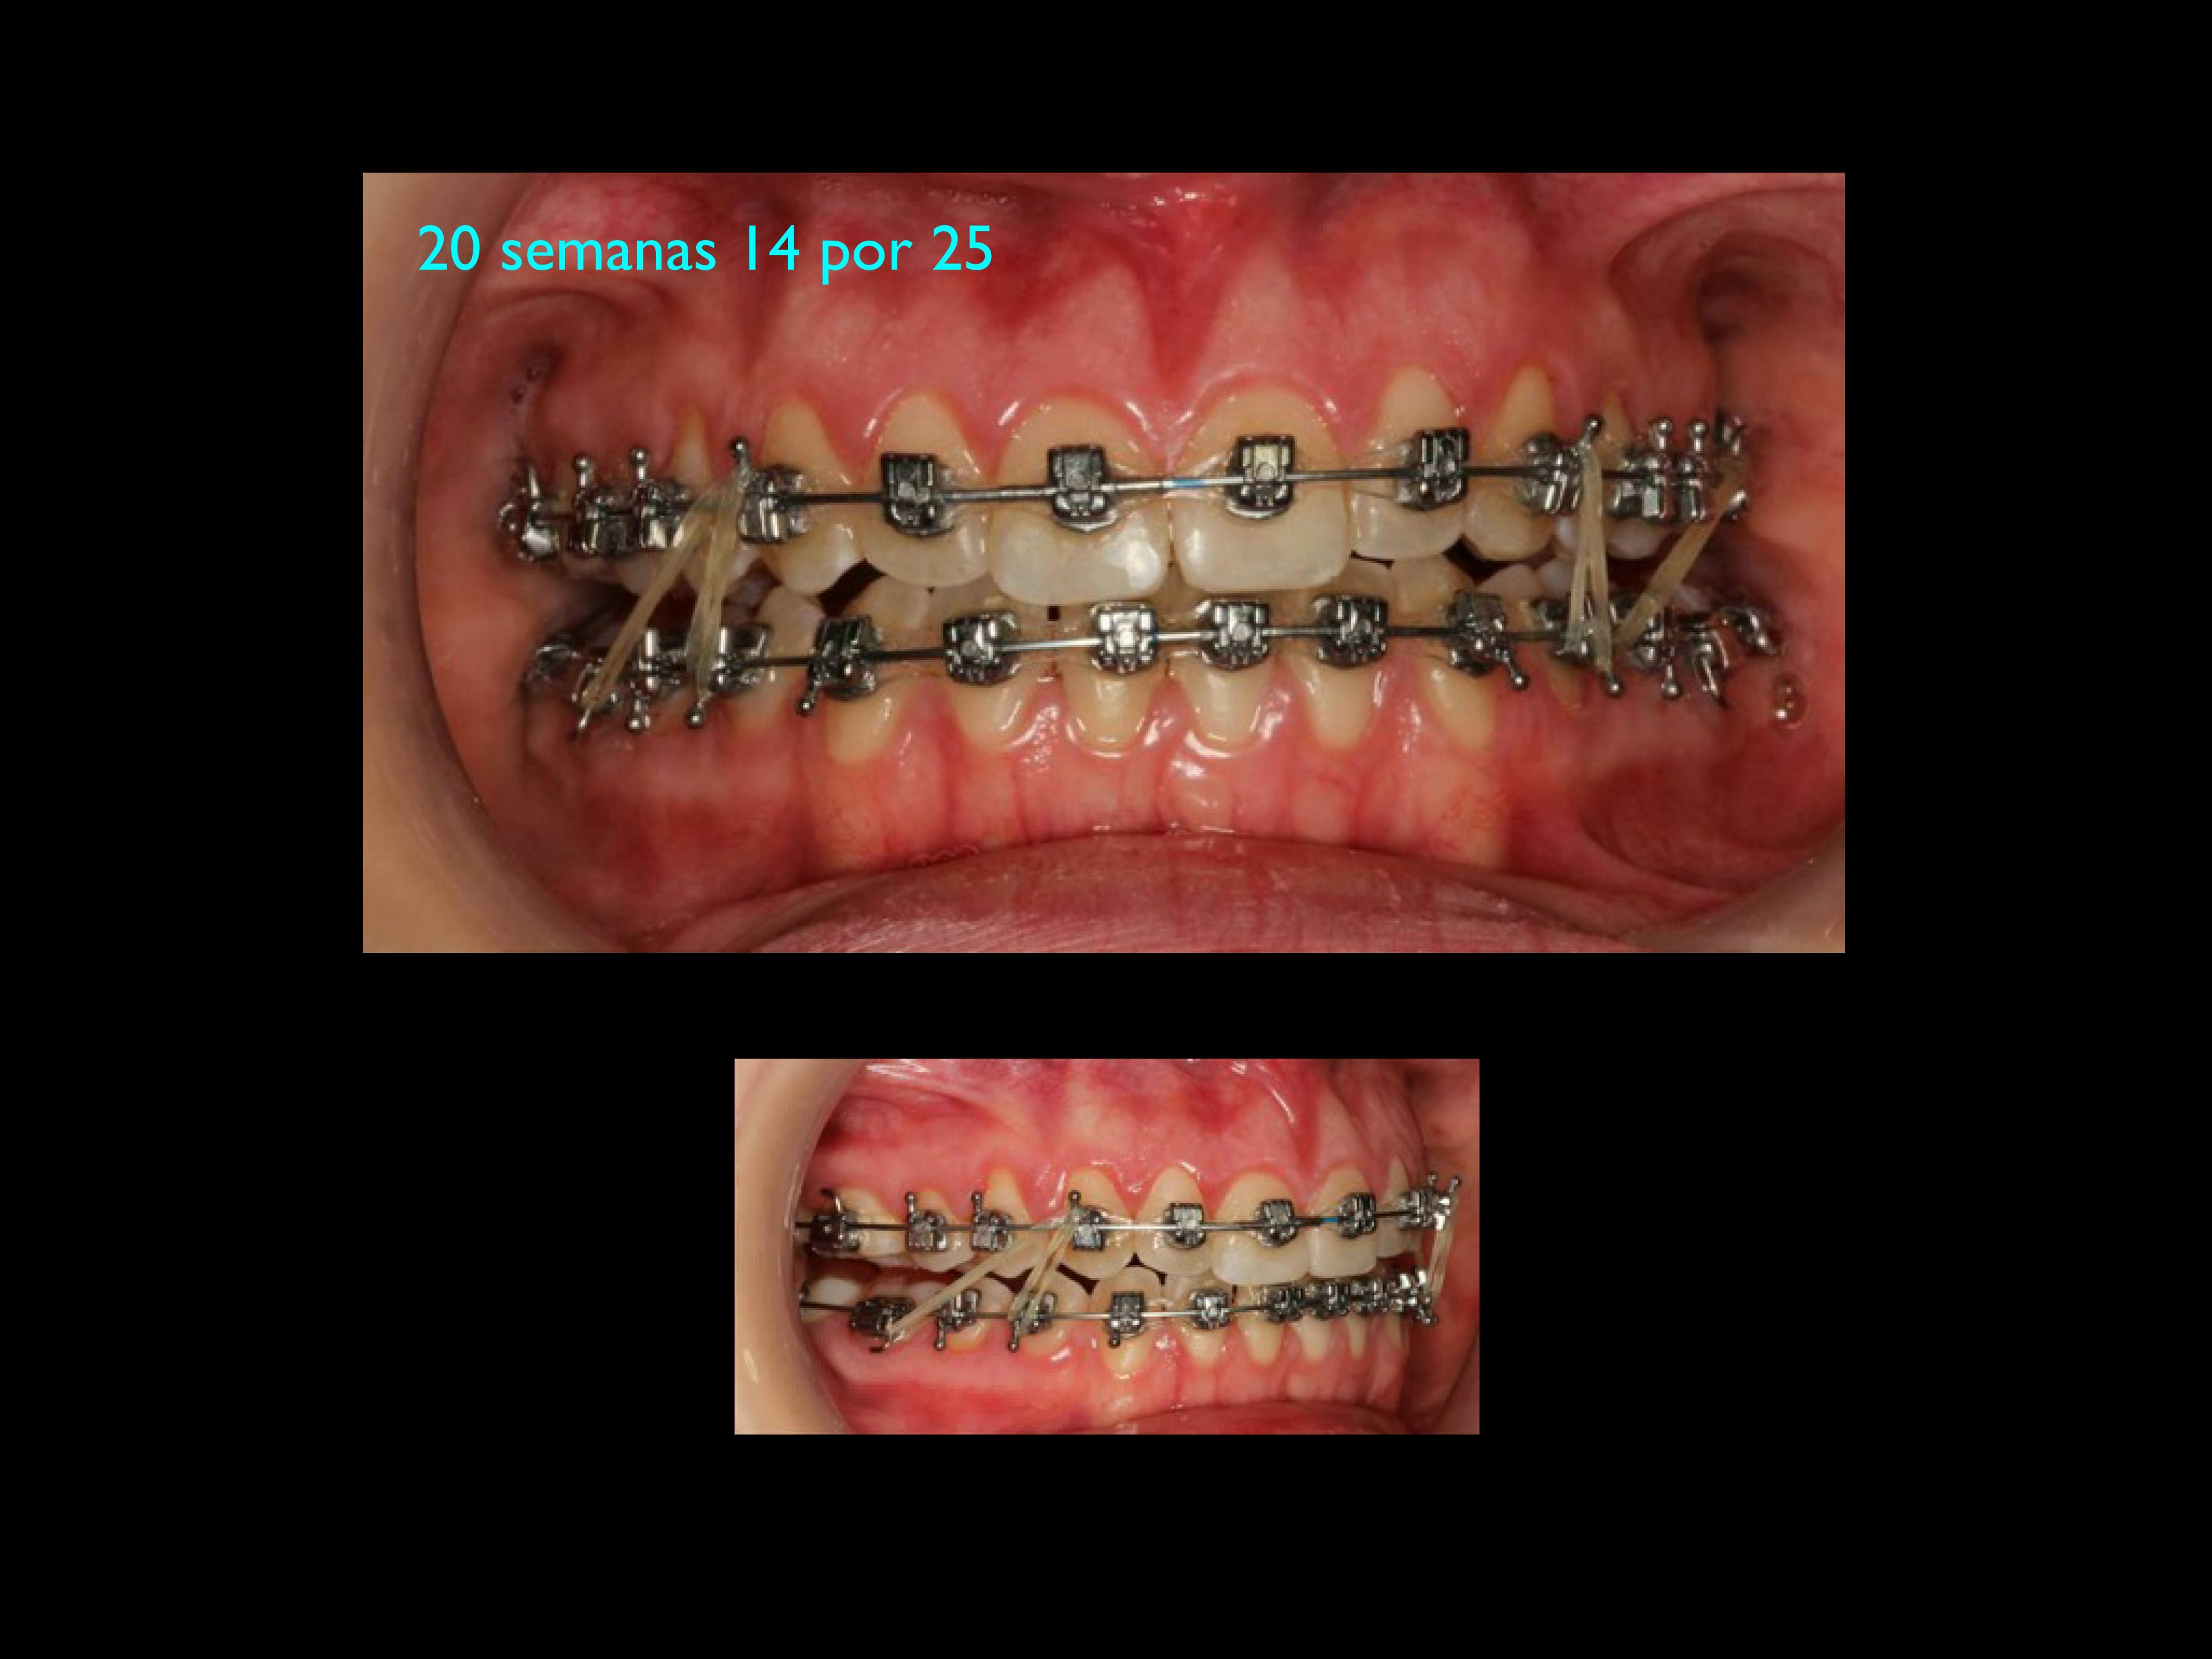

by Dr. Daniela Storino